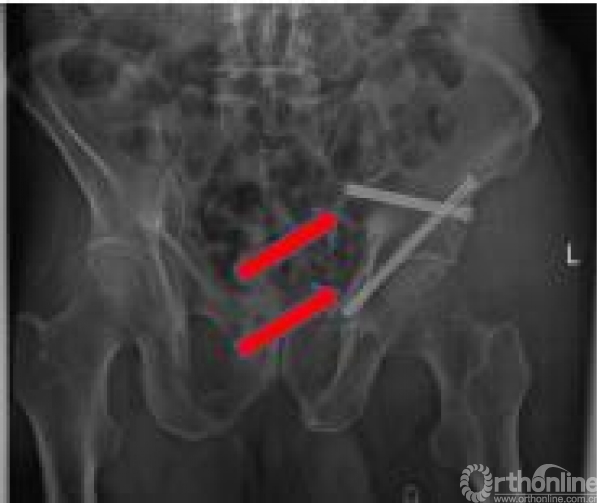

患者4 随访(B2型):经皮骶骨螺钉+INFIX前环内固定架